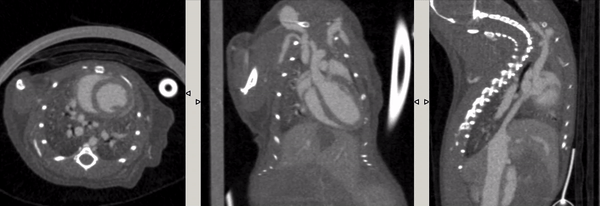

5、心跳/呼吸門控CT成像

心跳門控:活體小鼠注射顯影增強(qiáng)劑Exitron 12000,超高時(shí)間分辨率(10ms),成像時(shí)間:2min40s。

呼吸門控:超高時(shí)間分辨率(10ms),4min,390mGy。左圖:整體整合的圖。中圖:呼氣結(jié)束時(shí)的圖,右圖:吸氣結(jié)束時(shí)的圖,兩者顯示肺的容積相差34%。

圖13. 呼吸門控.png